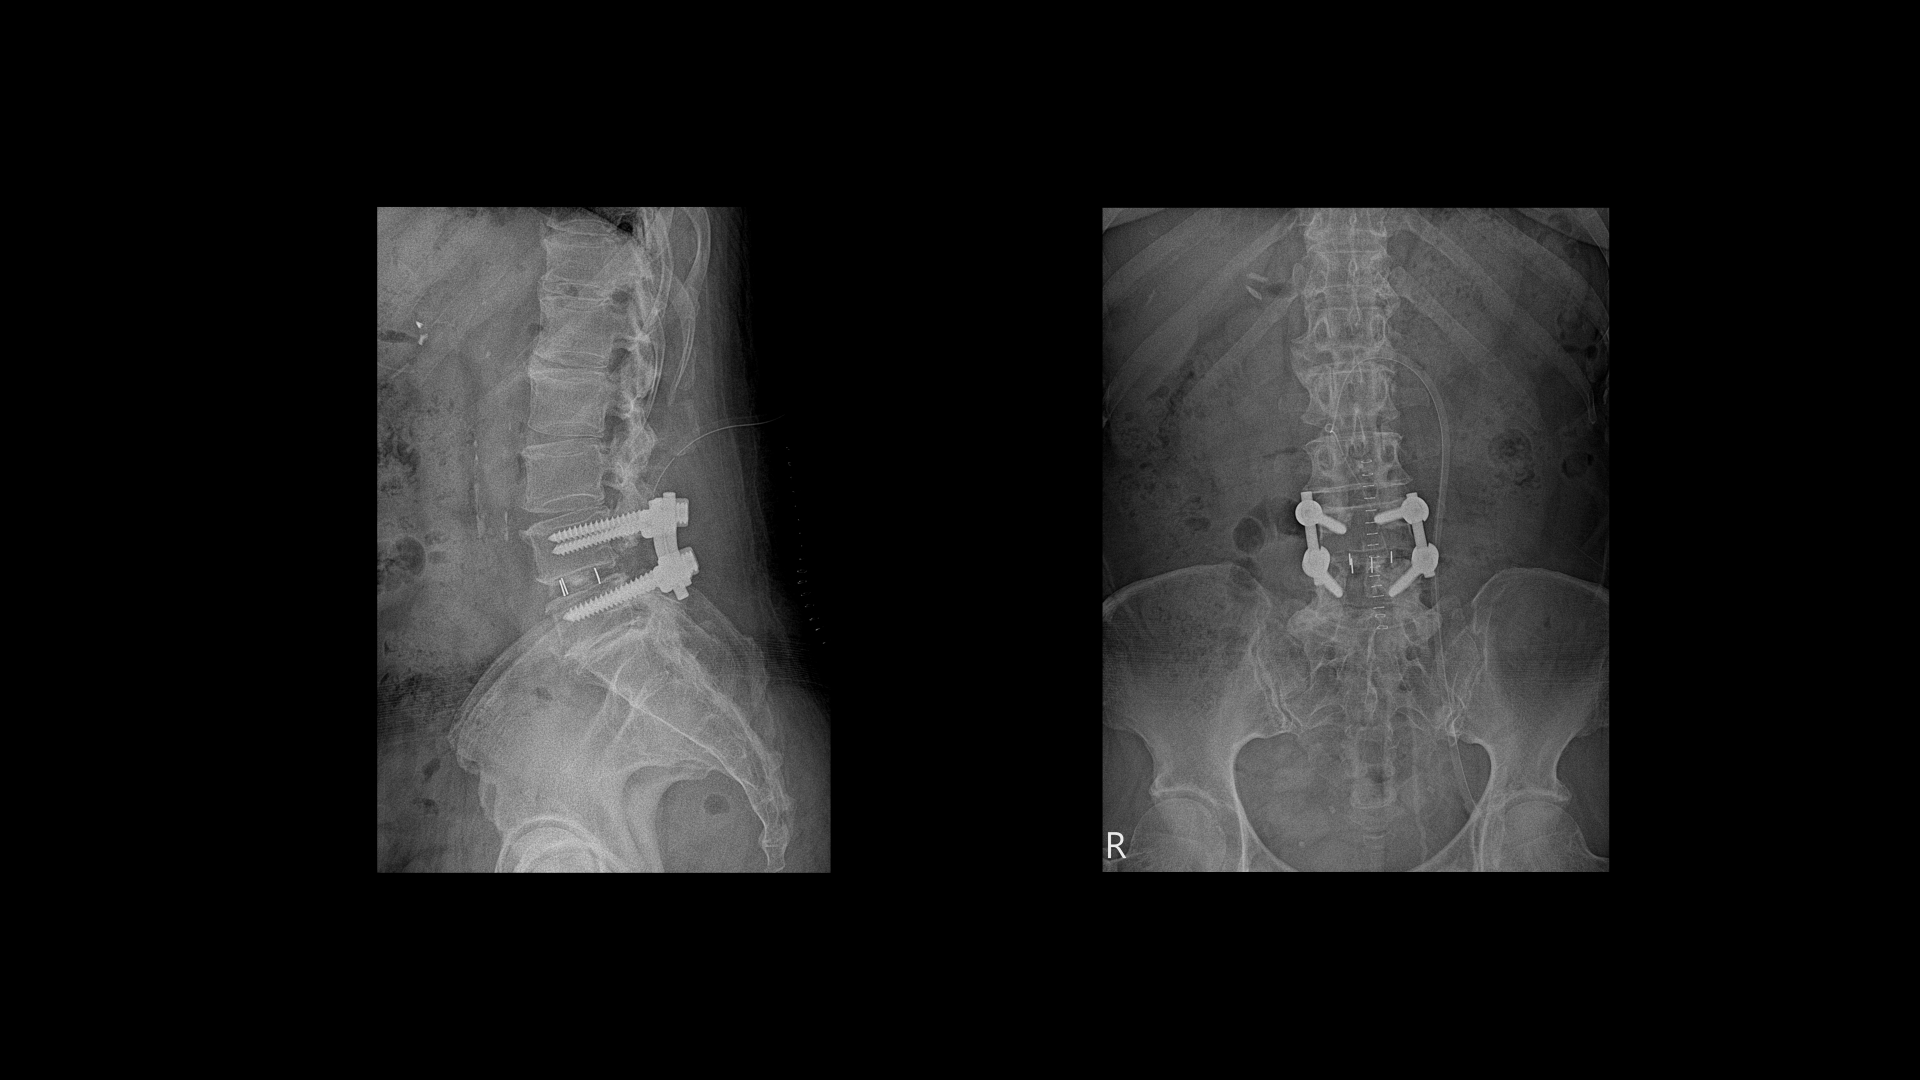

이 환자분은 허리수술을 여러 번 한 상태에서 결국에는 척추유합술까지 하셨습니다. MRI를 보시면 5번 1번 후궁에 수술한 자국이 보입니다.

4번 5번 후궁 양쪽으로 수술한 자국이 보입니다.

올해 초에 4번 5번 디스크가 또 오른쪽으로 심하게 파열돼서 결국 후궁과 후관절, 황색인대를 모두 다 제거하고 나사를 박는 척추유합술을 하셨습니다.